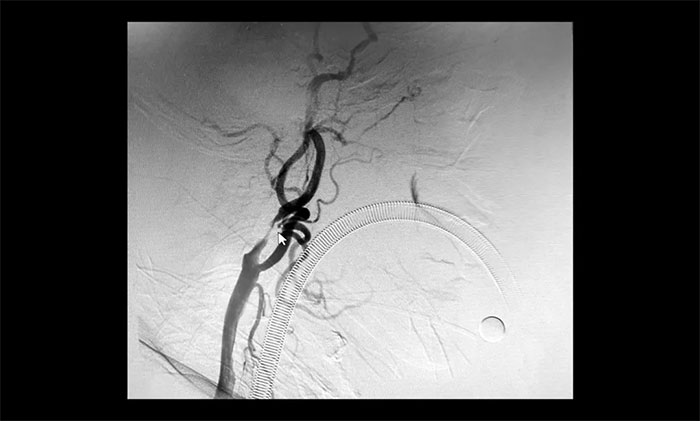

頸內(nèi)動(dòng)脈狹窄可分為輕度(<50%),中度(50%~69%)和重度(70%~99%),椎動(dòng)脈狹窄的判別標(biāo)準(zhǔn)與之相仿。DSA檢查示:患者雙側(cè)頸內(nèi)動(dòng)脈及左側(cè)椎動(dòng)脈存在重度狹窄,狹窄程度達(dá)到甚至超過(guò)90%,病情十分嚴(yán)重,遂立即收治入院。

▲ 雙側(cè)頸內(nèi)動(dòng)脈及左側(cè)椎動(dòng)脈重度狹窄